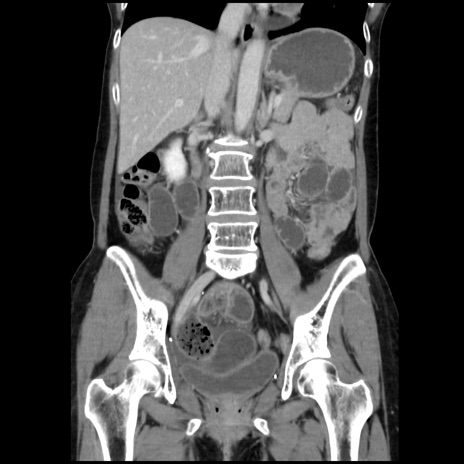

症例32(冠状断像)

【症例】40歳代 女性

【主訴】上腹部痛、嘔気・嘔吐

【現病歴】約9時間前頃から急に上腹部痛、嘔気、嘔吐が出現。改善しないため救急要請。

【既往歴】子宮頚癌(広汎子宮全摘術、放射線療法)、腸閉塞

【身体所見】腹部:平坦、軟、腸雑音亢進、上腹部を中心に腹部全体に圧痛あり。

【データ】WBC 8400、CRP 0.03